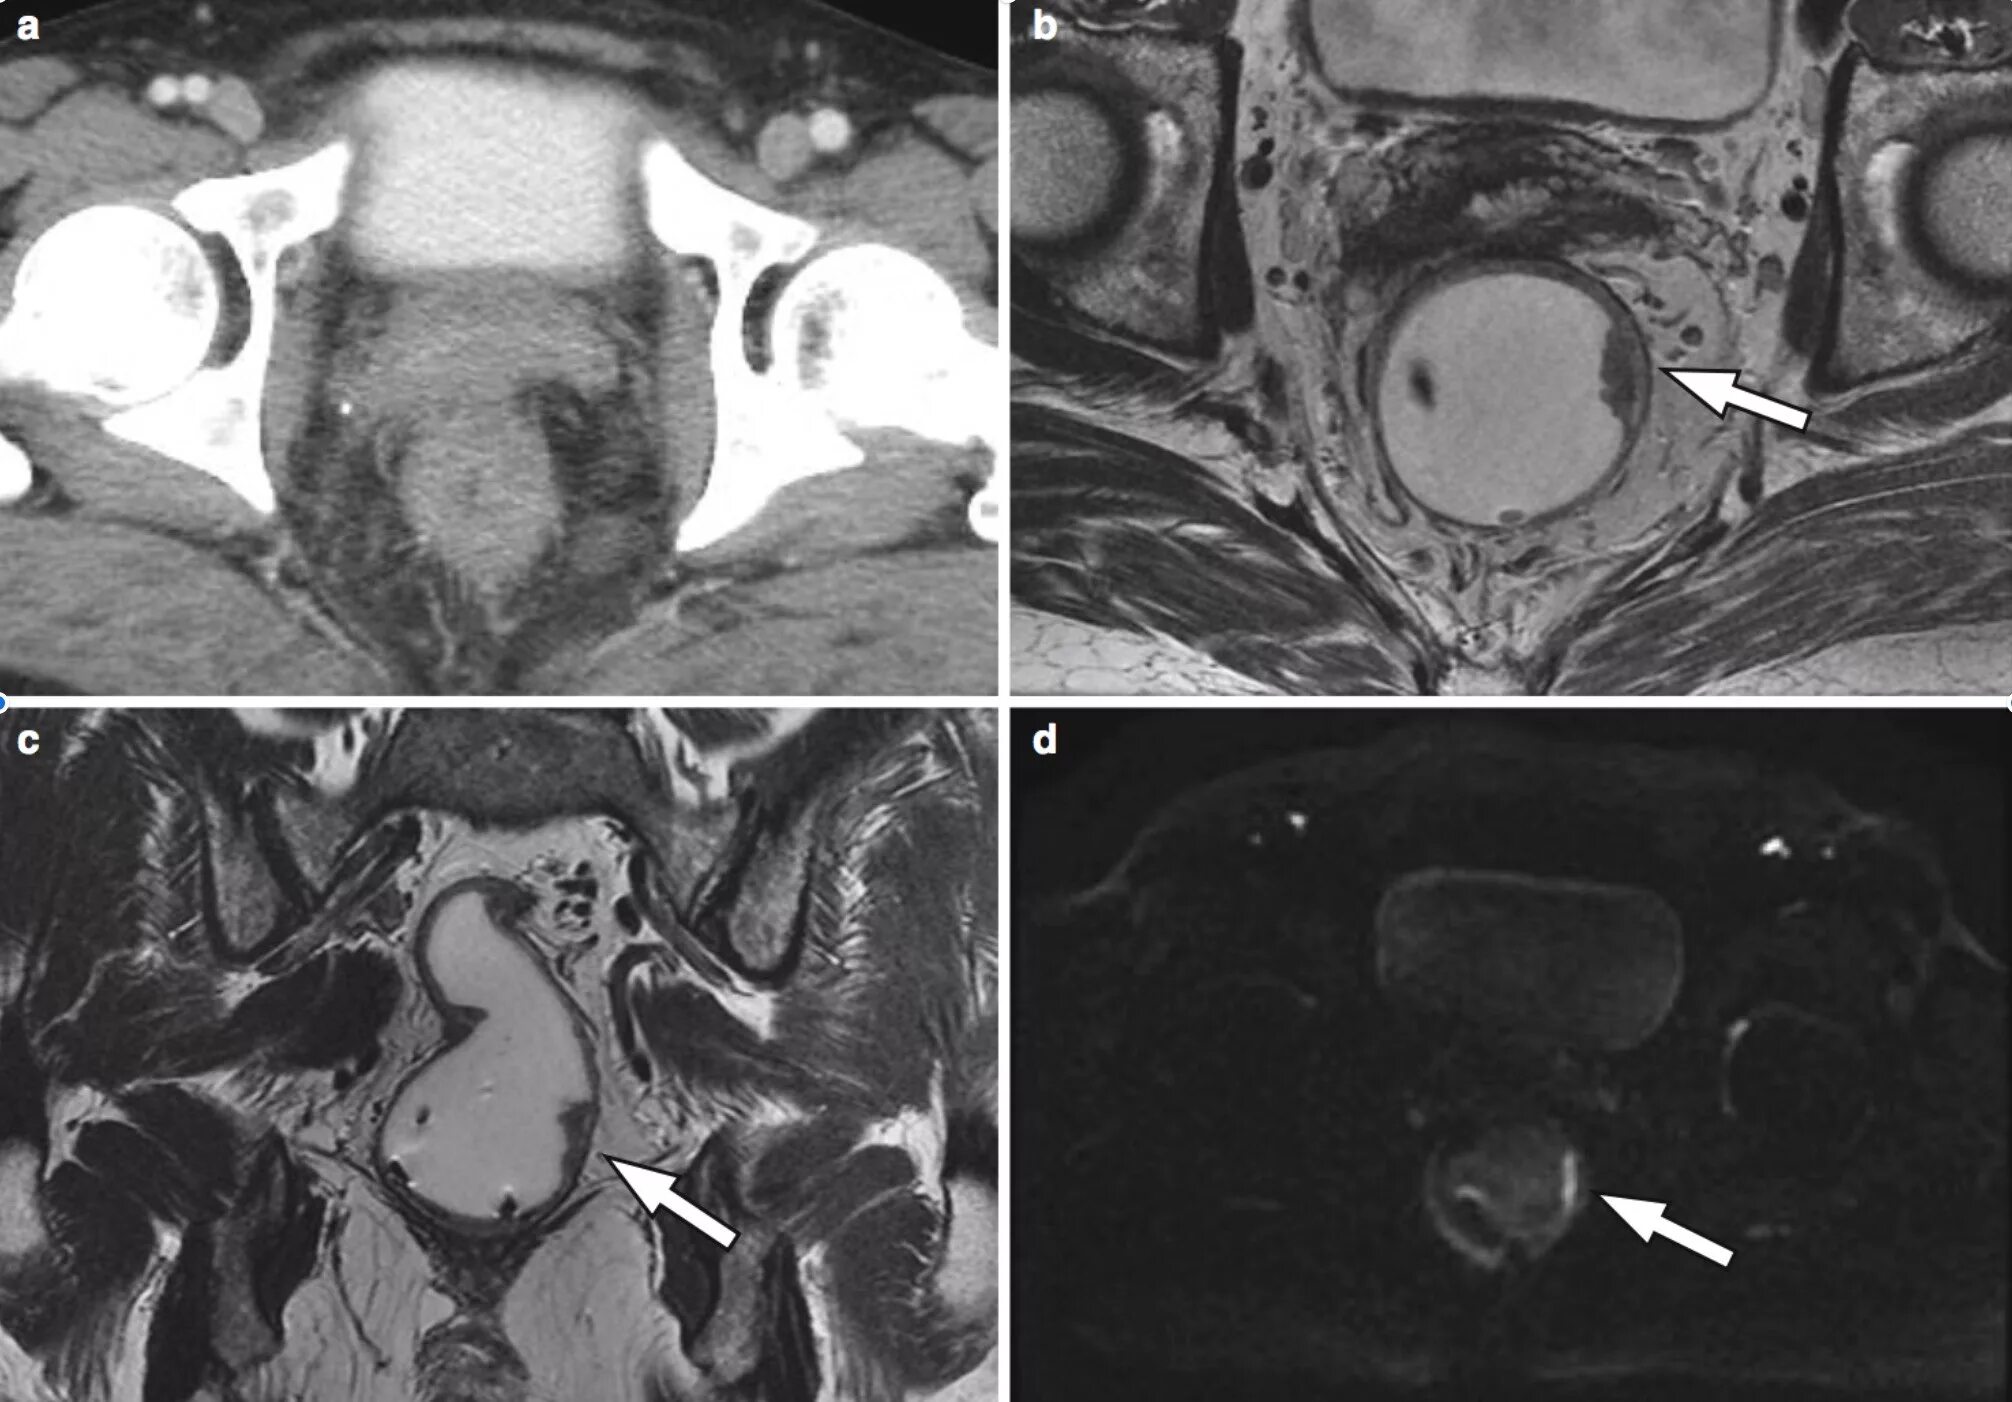

Метастазы при раке сигмовидной кишки